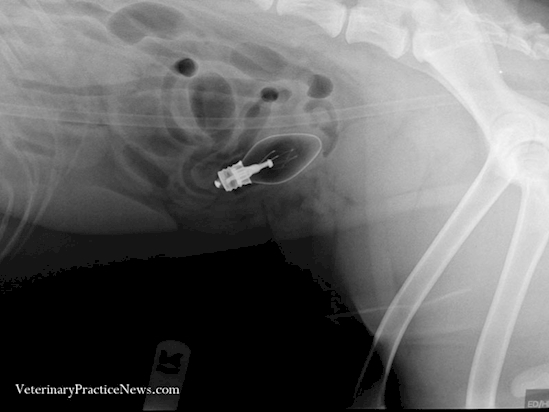

10. Meninggal setelah peluru bersarang pada tubuhnya selama 30 tahun

30 tahun yang lalu seorang pria dibawa ke rumah sakit karena mengalami luka tembak. Namun karena suatu hal, ada sedikit pecahan peluru yang bersarang di tubuhnya. Selama 30 tahun dia kemudian hidup normal dengan peluru yang masih bersarang pada tubuhnya. Sayang suatu hari, peluru itu ternyata menemukan jalan ke pembuluh darahnya dan membuatnya pecah dan berakibat serangan jantung yang membuatnya meninggal secara mendadak.